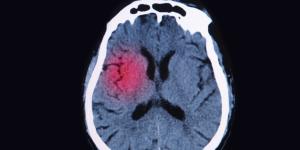

Un aneurisma es la dilatación de una arteria que termina formando una bolsa o bulto de sangre cuyo principal peligro es que el mismo se reviente, esta rotura tiene lugar por algún golpe, herida o ulceración. Cuando un aneurisma revienta se produce una hemorragia interna que puede comprometer seriamente la...